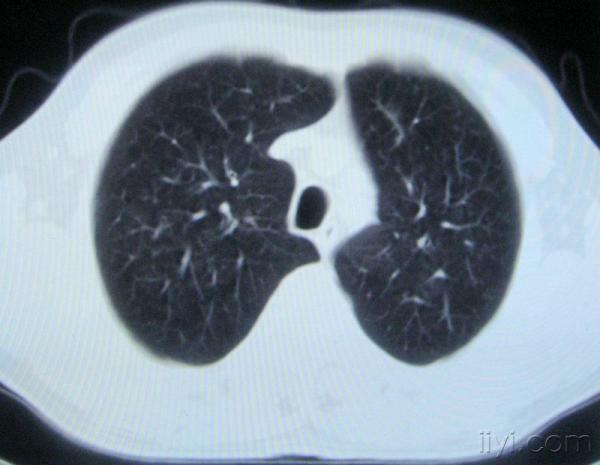

男。60岁,胸片示支气管炎治疗后复查CT。

你指那个肯定是淋巴结,中央系坏死,这很常见,特别在双侧腹股沟会经常看到。这个双侧腋窝及纵隔见多发小淋巴结征。

根据位置考虑应该是淋巴结,密度不均,是因为肿大的淋巴结中心液化坏死